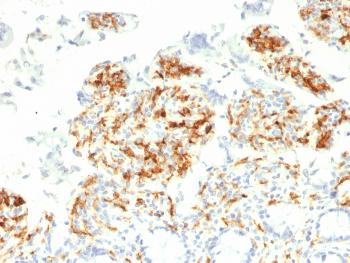

Fig. 1: Formalin-fixed, paraffin-embedded human Lung Carcinoma stained with CD209 Mouse Monoclonal Antibody (C209/1781).

Western Blot (1-2ug/ml); Immunohistochemistry (Formalin-fixed) (1-2ug/ml for 30 minutes at RT),(Staining of formalin-fixed tissues is enhanced by heating tissue sections in 10mM Tris with 1mM EDTA Buffer, pH 9.0, for 45 min at 95°C followed by cooling at RT for 20 minutes),